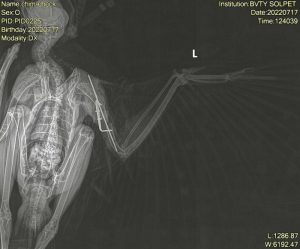

Máy X-quang kỹ thuật số Tutom 100

- Thực hiện các thao tác về chẩn đoán hình ảnh như siêu âm, chụp x-quang.

Phẫu thuật kết hợp xương trên một chú chim Ưng bị gãy xương cánh tay bằng Phương pháp cố định đinh nội tủy và bộ cố định bên ngoài